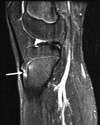

Figure 11.

16-year-old female runner with prior history of pelvic stress fracture, now complaining of tibial pain. Sagittal STIR image demonstrates edema at the insertion of the patellar ligament (arrow), consistent with active Osgood Schlatter disease. There is mild pretibial edema in the soft tissues anterior to the tuberosity. There is minimally increased signal within the ligament itself.

Figure 12.

3-year-old girl with a limp. Lateral radiograph demonstrates an area of uninterrupted periosteal reaction along the posteromedial aspect of the left tibia at the middle third of the tibia, consistent with stress fracture.